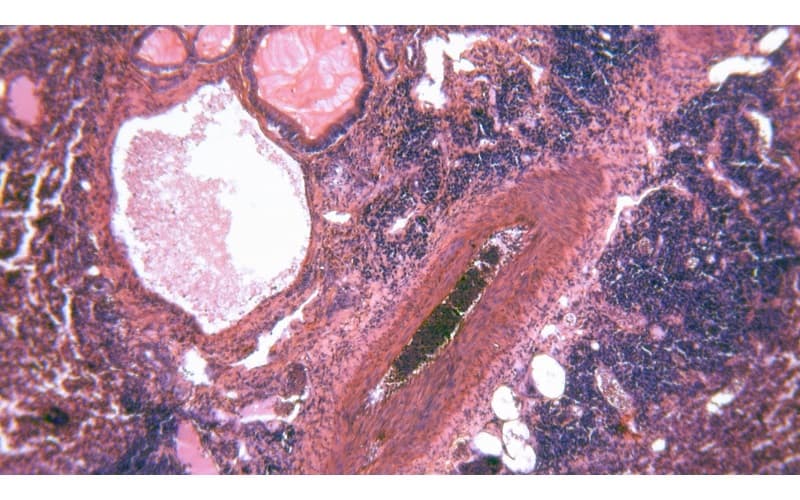

Áp xe phổi là tình trạng nhiễm trùng sâu bên trong nhu mô phổi, hình thành các ổ mủ. Nếu không được điều trị kịp thời bằng kháng sinh hoặc điều trị không hiệu quả, người bệnh có thể phải đối mặt với nhiều biến chứng áp xe phổi nguy hiểm, thậm chí đe dọa đến tính mạng.

Tình trạng hoại tử nhu mô phổi diễn ra nhanh chóng, đặc biệt ở bệnh nhân có hệ miễn dịch suy yếu. Mô phổi bị phá hủy nghiêm trọng, ảnh hưởng đến chức năng hô hấp và gia tăng nguy cơ tử vong nếu không được can thiệp tích cực.

Khi ổ áp xe vỡ vào khoang màng phổi, sẽ gây ra tình trạng tràn mủ màng phổi – một biến chứng nguy hiểm cần can thiệp ngoại khoa. Tình trạng này làm suy giảm chức năng hô hấp nghiêm trọng và có thể gây biến chứng nhiễm trùng lan rộng.